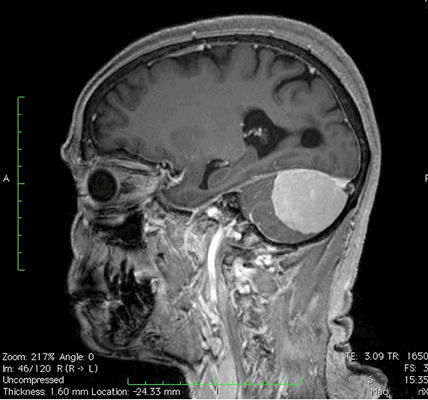

МР-сканирование при подозрении на менингиому мостомозжечкового угла, сагиттальная проекция

В диагностике патологических изменений ЦНС в области ствола используют МРТ головного мозга с прицельным осмотром мосто-мозжечкового угла (ММУ). Сканирование необходимо для уточнения состояния данного участка и выявления патологических изменений нервных корешков.

Магнитно-резонансная томография отличается большей информативностью в отношении исследования тканей, клетки которых содержат достаточное количество жидкости. При сканировании с прицельным обследованием мосто-мозжечкового угла получают детальные изображения церебральных структур. Для повышения результативности используют МРТ с контрастным усилением.

МР-сканирование головного мозга с прицельным изучением мосто-мозжечкового угла, фронтальный срез

«Окрашивающий» раствор заполняет просвет вен и артерий, межклеточное пространство в исследуемой зоне. На снимках появляется четкий рисунок сети кровеносных сосудов, хорошо видны аномалии строения (петли, анастомозы, аневризмы и пр.), определяется зона компрессии корешка черепно-мозгового нерва при вазоневральном конфликте.

При использовании контраста МРТ визуализирует новообразования, диаметр которых не превышает 3 мм. Ткани опухоли накапливают усиливающий препарат, сосудистая сеть, в зависимости от степени малигнизации (озлокачествления), имеет характерный рисунок. На основании полученных изображений рентгенолог может предположить характер процесса, окончательный диагноз ставит лечащий врач.